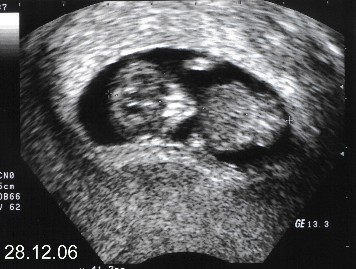

28.12. haben sie mich dann auf dem Monitor beim Ultraschall gesehen, ups ich war ja schon fast 3 Monate.....